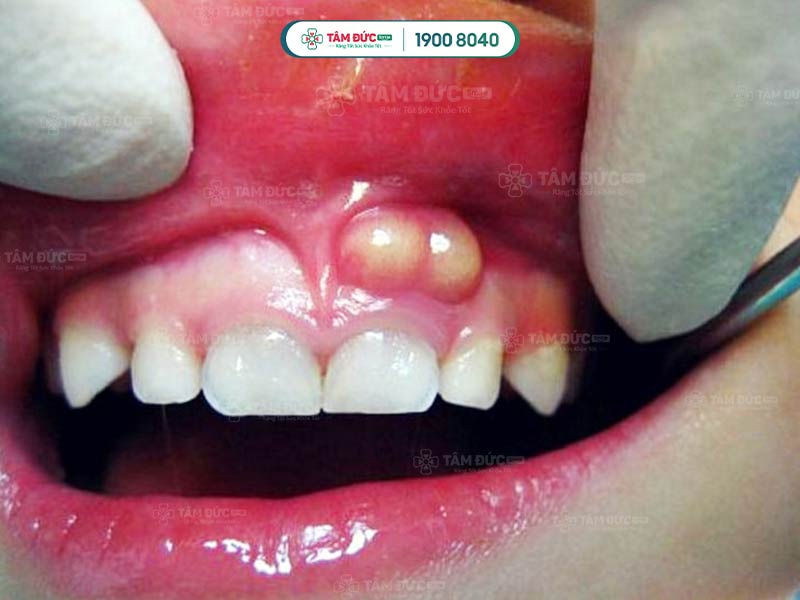

Áp xe răng là biểu hiện vi khuẩn đã tấn công vào chân răng

Thứ tư: Bị sưng vùng lợi ở dưới chân răng, có khả năng xuất hiện cả những hạt mủ tụ ở dưới chân răng.

Thực tế, triệu chứng của bệnh viêm tủy áp xe răng khá dễ nhận biết bằng mắt thường. Nếu ổ áp xe càng lớn thì chứng tỏ bệnh đã diễn biến nặng, dễ gây ảnh hưởng tới dây thần kinh và các mô. Bệnh này có thể xuất phát từ nhiều nguyên nhân khác nhau, trong đó có thể kể tới như: